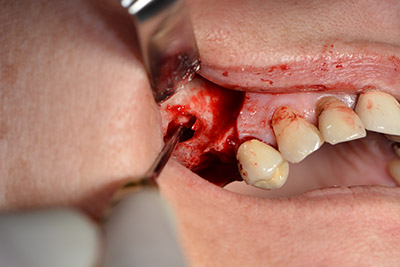

The next step was the sinus floor elevation with simultaneous implantation. The Implantmed also had a presetting at the first position for the buccal fenestration of the maxillary sinus wall.

The fenestration was prepared at 35,000 rpm and then the nasal mucosa were prepared in the cranial direction (Fig. 13 to 14).